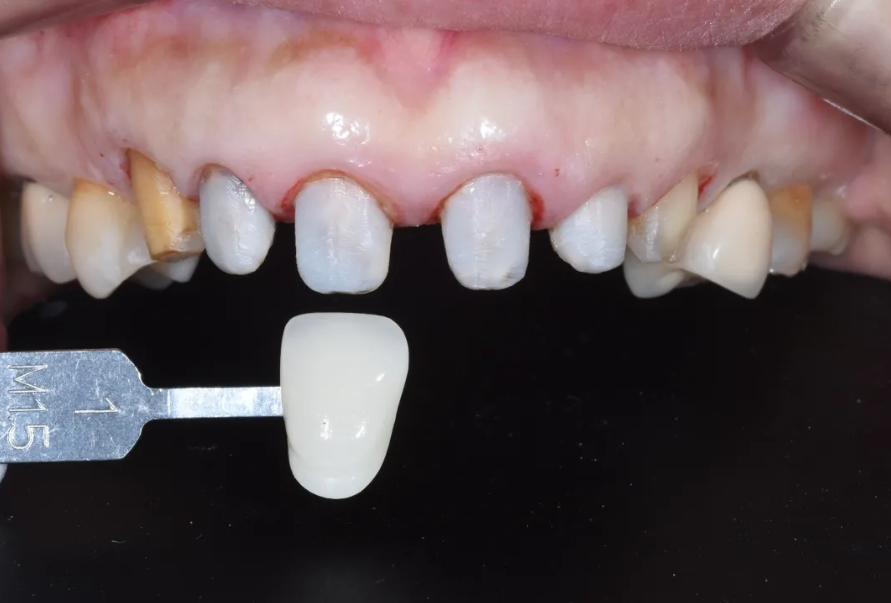

치료 과정 STEP 2 – 우식 제거 및 코어 빌드업

다음 단계로, 발견된 충치를 깨끗하게 제거했습니다. 그 후 밝은 색 레진을 이용하여 코어 빌드업을 진행했습니다.

코어 빌드업이란, 치아의 손상된 부분을 레진 같은 재료로 채워서 크라운이 안정적으로 올라갈 수 있는 기둥을 만드는 과정입니다. 이때 밝은 톤의 레진 재료를 사용한 이유는, 최종 크라운의 색감에 어두운 색이 비치지 않도록 하기 위해서입니다. 특히 심미성이 중요한 앞니 부위에서는 이런 세심한 부분이 결과에 큰 영향을 줍니다.

충치 제거 후 밝은 색 레진으로 코어 빌드업을 완료한 모습

남아 있는 치아 양이 충분치 않았지만, 코어 빌드업으로 보강하여 크라운이 안정적으로 유지될 수 있는 지지력을 확보했습니다. 이후 치아를 다듬고(지대치 형성), 본을 뜬 다음(인상 채득), 임시 크라운을 장착해 드렸습니다. 환자분은 이 임시 크라운 상태로 일본으로 돌아가셔서 약 3개월간 생활하셨습니다.